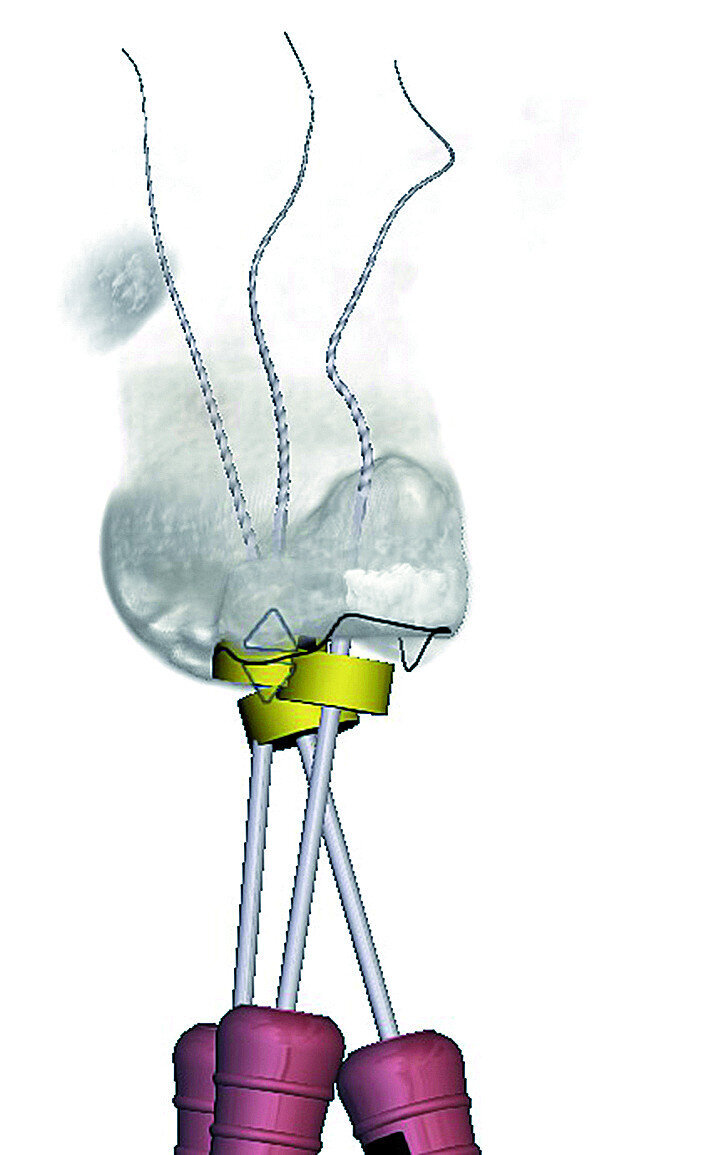

During the fifth step, ‘Treatment Plan’, the software projected ISO size 06 instruments into the canals (Fig. 11), which allowed the operator to visualise the internal anatomy of the canals, check straight line access, and modify the proposed access if necessary. A rubber stop on the files can then be digitally adjusted to a coronal reference point of choice that will then indicate the proposed working length for each root canal system. This view can also be rotated in 3-D to alert the operator of the angle and direction of curvatures in the root canal systems (Fig. 12). The step after ‘treatment plan’ is to select a master file from a preloaded database of endodontic file systems that will most likely result in optimal canal preparation for that specific shape or diameter of a canal. Considering the s-shaped curvatures in all three root canal systems as well as the sharp curvatures in different planes, it was decided to use the Primary WaveOne Gold file (25/07) in the palatal canal and the Small WaveOne Gold file (20/07) for root canal preparation in the two-challenging buccal root canal systems (Fig. 13). The selected instruments were then displayed in the root canal systems and the operator again digitally rotated and visualised the root canal anatomy in 3-D (Fig. 14).

The 3D Endo Software that was used in this case report not only allowed the operator to scroll through the tomographic slices in the coronal, axial and sagittal planes, but facilitated a 3-D image of the root canal anatomy prior to treatment. Only after visualising the severe curvatures and their projection in the buccal palatal direction was the complexity of this case realised. This information was vital for the treatment-planning phase of this case. According to the information obtained from the 3D Endo Software, the authors could select the ideal instruments for canal negotiation, glide path and canal preparation, irrigation and obturation. According to Tchorz (2017), the option to plan endodontic cases in 3-D before treatment is a significant gain for modern endodontics, and can help to prevent procedural errors, especially in complex cases. [10] It is important to note that in this case report the working length measurements obtained from the 3D Endo Software and the apex locator correlated with each other. However, it always advised to verify the software readings with an apex locator, as several parameters such as the access cavity design and position, the amount of coronal preflaring and the choice of reference point can have an influence on the working length measurement. [10]

The preoperative planning stage using the 3D Endo Software provided the authors with vital information regarding the complex root canal anatomy that influenced the choice of materials and techniques in this case report. Because the root canal anatomy could be visualised in 3-D preoperatively, the authors realised that there would be a high risk of either losing working length or instrument fracture during canal preparation. It was therefore very important to secure the canals by means of glide path preparation and enlargement prior to root canal preparation.